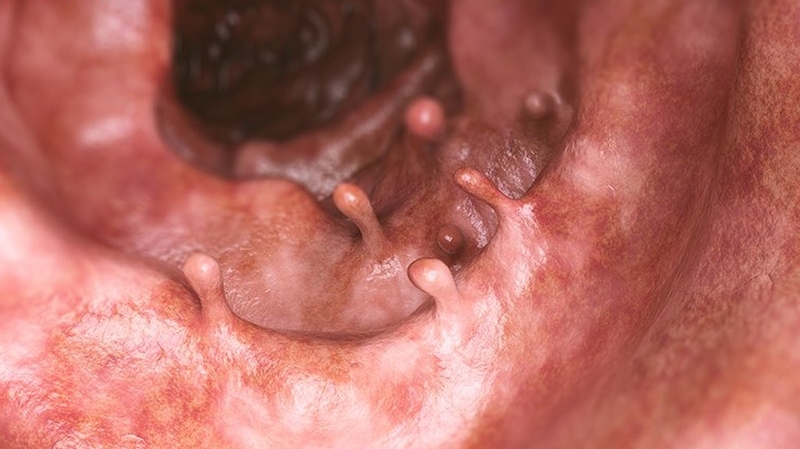

Polyp trực tràng hình thành do sự tăng sinh quá mức của niêm mạc trực tràng. Đa số các trường hợp polyp đều là lành tính. Tuy nhiên, vẫn có một tỷ lệ nhỏ tiến triển thành ung thư trực tràng nếu không được theo dõi và điều trị kịp thời.

Có 2 dạng polyp trực tràng phổ biến là polyp không cuống (polyp phẳng) và polyp có cuống. Trong đó, thường gặp nhất là polyp không cuống.

Tiếp đến, bác sĩ sẽ sử dụng một sợi dây thòng lọng luồn qua ống nội soi và đưa ống nội soi vào trực tràng qua đường hậu môn. Dây thòng lọng sẽ được đặt dưới đáy của polyp và dùng để cắt rời cuống polyp sau khi đốt đáy bằng dòng điện. Tùy vào hình dạng và kích thước polyp mà bác sĩ nội soi sẽ lựa chọn phương pháp loại bỏ phù hợp. Sau khi cắt, mẫu polyp sẽ được đưa đi sinh thiết để đánh giá xem là u lành tính hay ác tính.